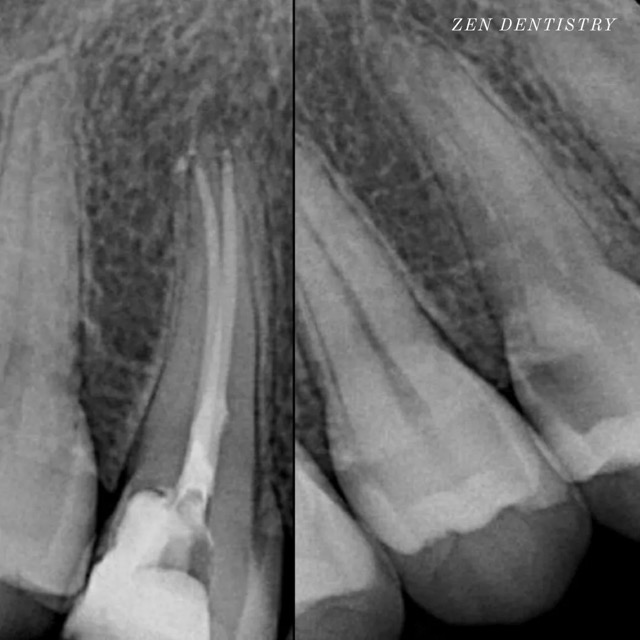

Patient presented to the office with a concern that the tooth has been causing severe constant pain that would become worse at night time and biting. A detailed clinical exams including endodontic screening and x rays let to the diagnosis of irreversible pulpitis (inflammation of the nerve) due to existing filling that was very close to the pulp and symptomatic apical periodontitis (inflamed ligaments).

The tooth was taken out of the bite and pain medication was prescribed to see if the pain could be resolved without having to do a RCT. However tooth responded in the same manner after a week. So it was decided to do a RCT. Root Canal treatment was performed that included removing the caries, dead nerve tissue and disinfecting the canals with proper medication to achieve a 3D hermetic seal of the canals to save the tooth.